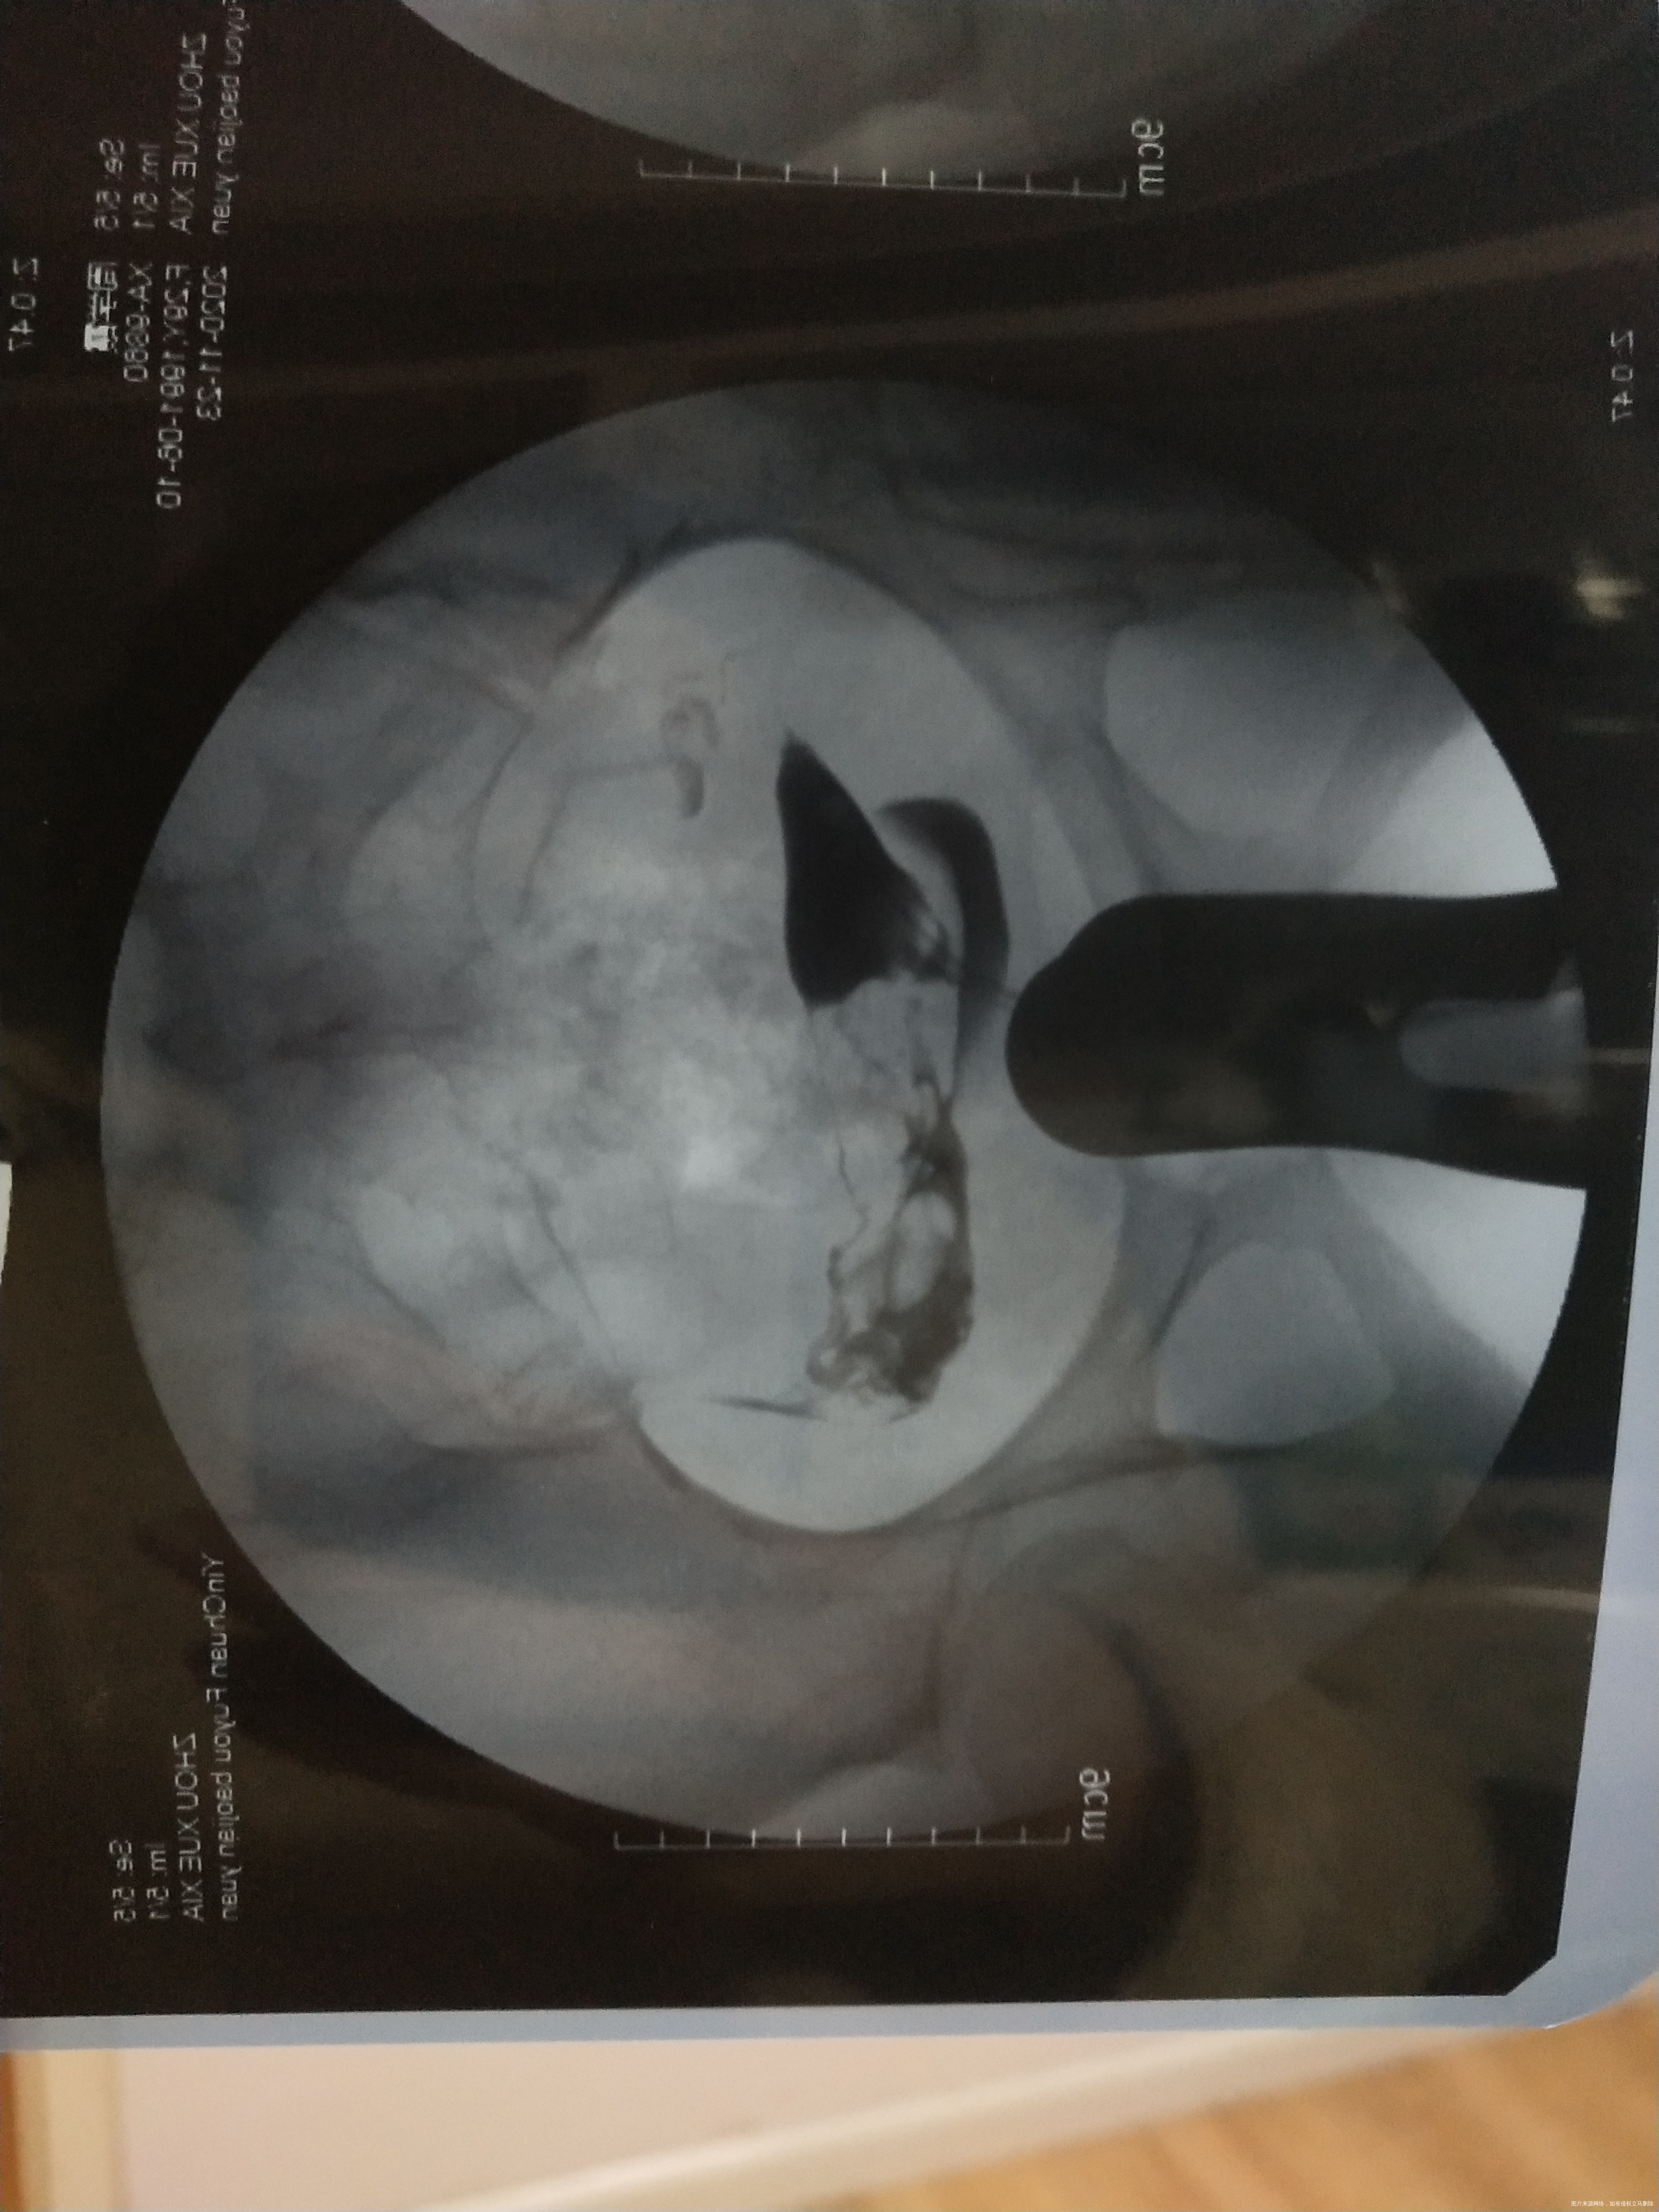

备孕两年,之前检测卵泡不破裂,有过5年的慢性阑尾炎,做了手术2年了,输卵管造影右侧不通,您看一下是做手术比较好还是先试着用左侧输卵管的去怀呢

您好,建议先用左侧去试,因为阑尾炎病史较长,右侧手术的话输卵管功能估计也不能完全恢复。男方精液检查一下,如果没有问题,也可以考虑人工授精3-6周期试试

回复 陈淑萍:那大夫左边这个是完全通畅吗?

陈淑萍 回复 :不好意思,这个图我这样不能直接判断,不清楚,拿给你的主治医生瞧瞧